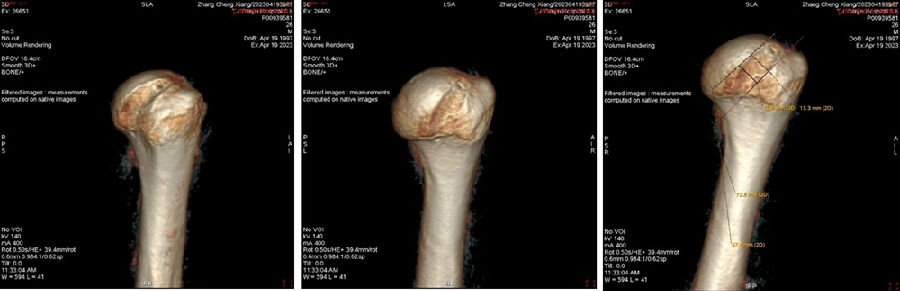

Case1:影像学评估病例,19岁,打篮球摔伤脱位。

图23 首次脱位

图24 打球再次受伤,复发脱位

图 25-27 MRI

双侧CT三维扫描显示:健侧肩胛盂宽度D=25.9,患侧D=23.9,患侧肩胛盂骨性缺损d=6.2,骨性盂唇缺损面积d/D为23.9%(<25%)。肩胛盂轨迹GT(83%D-d)为15.3mm。

图28双侧CT三维扫描

图29 Hill-Sachs间隙为13.8mm(<15.3mm)

图30 评估结果

评估报告提示:右肩胛骨关节盂前下缘撕脱骨折,符合骨性bankart损伤。右肱骨头后上缘凹陷骨折,符合Hill-Sachs损伤。Hill-Sachs间隙为13.8mm(<15.3mm),为轨迹内肩关节前脱位。